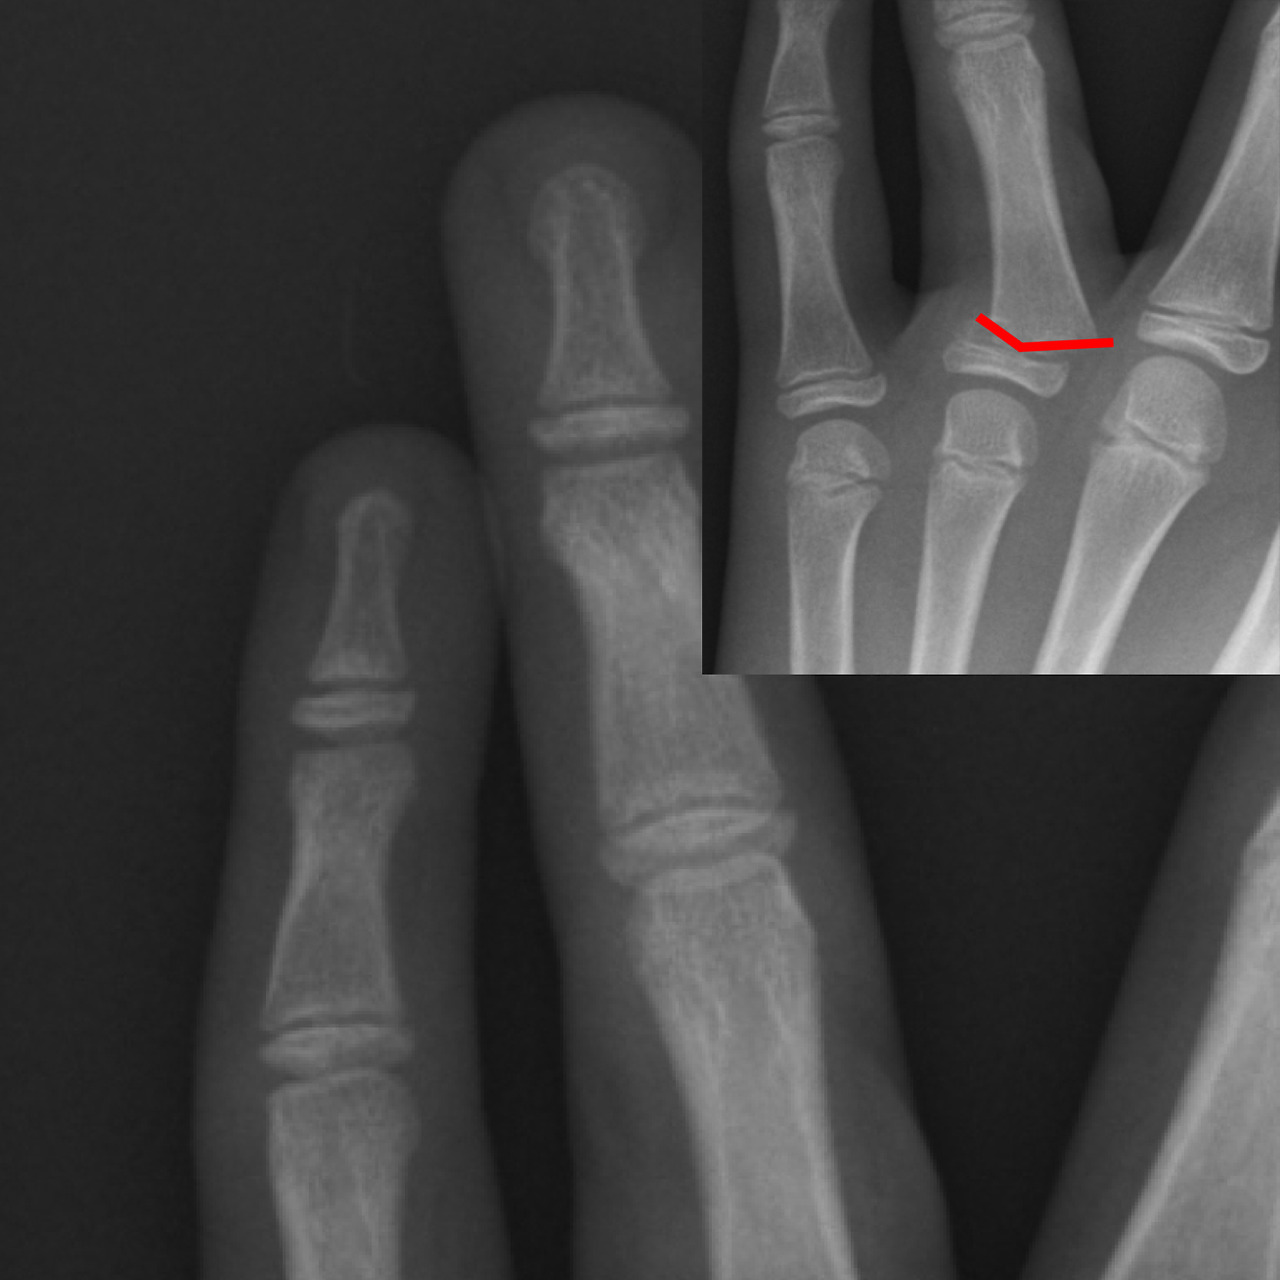

손가락 골절 스플린트 치료

손가락 골절에서 스플린트는 가장 기본적이면서도 중요한 치료 수단입니다. 손가락은 작은 뼈들이 관절과 밀접하게 연결되어 있어, 정확한 위치 고정이 이루어지지 않으면 기능 저하로 이어질 가능성이 높습니다.

손가락 스플린트는 골절 위치에 따라 착용 각도와 형태가 달라집니다. 예를 들어 말단지 골절의 경우 손끝만 고정하는 단순 스플린트가 사용되며, 중간 마디나 관절 침범 골절의 경우 손가락 전체를 포함하는 고정이 필요할 수 있습니다. 스플린트 착용 기간은 대개 3-6주이며, 이후에는 점진적인 관절 운동이 병행됩니다.